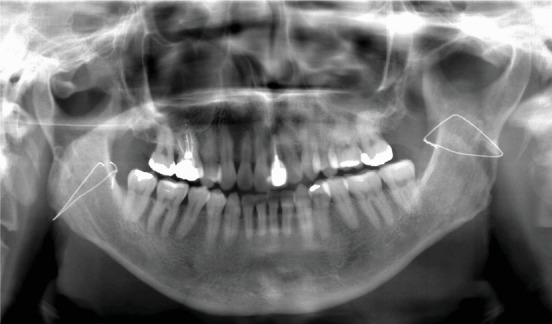

We present a case of solitary neurofibroma in the masseter muscle that was excised via the high perimandibular approach (HPMA). A 52-year-old Japanese man complained of an uncomfortable feeling in his right buccal region. On examination, the buccal mucosa appeared normal, and overall, there were no skin disorders on the patient's body. Computed tomography revealed a well-defined 33 × 22-mm mass in the right masseter muscle showing a low density in the center and a slightly higher density at the margin of the mass. Magnetic resonance imaging also showed a hyperintense area on T1-weighted and T2-weighted images in the masseter muscle. An excisional biopsy was scheduled for the diagnosis of the intramasseteric mass. It was performed via the HPMA with the patient under general anesthesia. The final diagnosis was a neurofibroma. The patient recovered after the surgery without postoperative complications, including facial nerve damage and trismus. He was satisfied with the esthetic outcome, and the tumor has not recurred over a 24-month follow-up period. Altogether, these outcomes indicate that the HPMA is an effective and useful option for excision of a tumor in the masseter muscle.